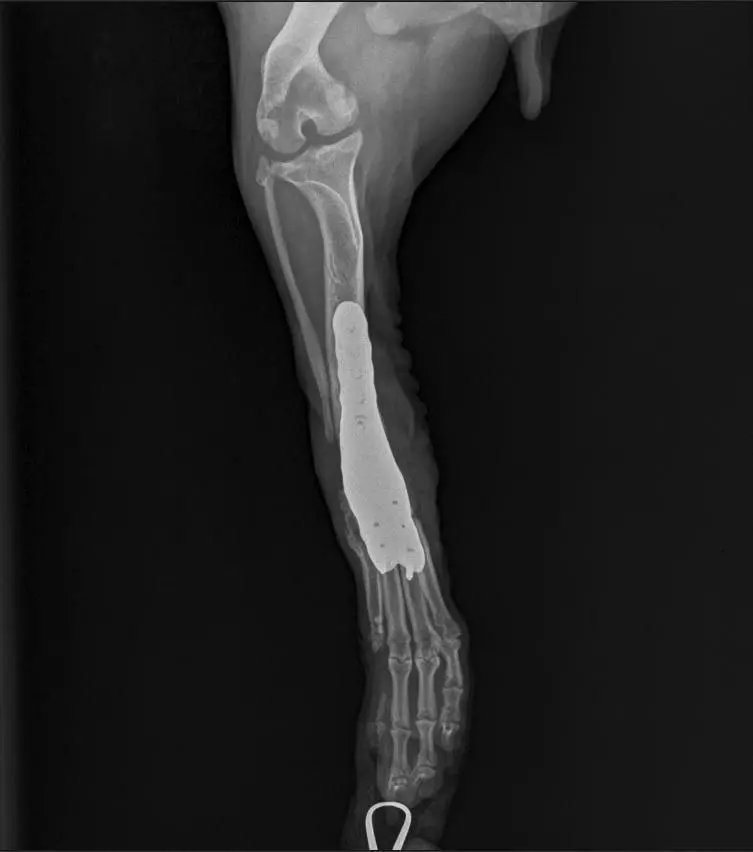

Псу с параличом из города Сальска установили индивидуальный титановый протез для лапы. Информацию об этом порталу DonDay рассказала Юлия Адимова, владелица приюта в Сальске.

Так, 30 октября врачи провели операцию Мите. Оперативное вмешательство прошло успешно.

Однако существует высокая вероятность инфекции. Полная картина по итогам операции будет понятна после двух недель. Если инфекция все же появится, то диск придется убирать и оставлять все как есть.